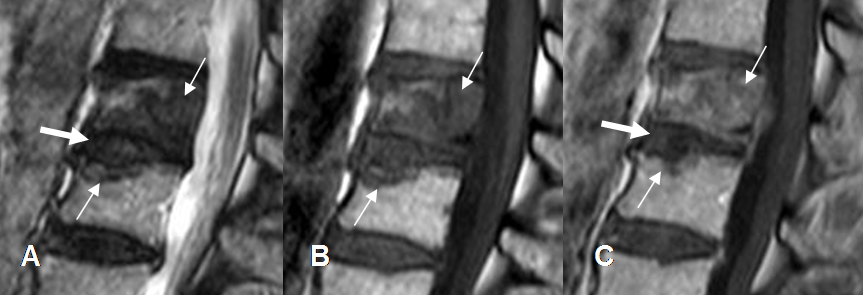

Fig 141 C. Diferencial de espondilodisquitis. Igual paciente anterior.

A: RM sagital en T2, B: RM sagital en T1 simple y C: RM sagital en T1 con contraste.

Cambios inflamatorios en la porción anterior del disco, siendo hiperintensa en T2 y con realce del contraste, por espondilodisquitis.